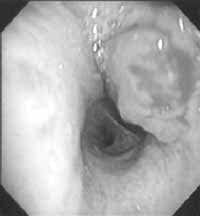

Figura 1. Tumor carcinoide endobronquial de localización central.

Los carcinoides pueden ser centrales o periféricos (2), y su localización no se relaciona con el tipo histológico del tumor. Entre un 16 – 40% de los tumores carcinoides son periféricos (8), y se localizan a nivel subpleural sin relación anatómica con el bronquio (8). De igual forma pueden aparecer asociados a la fibrosis pulmonar idiopática, así como a los adenocarcinomas (2).

Cortesia del Dr. Carlos Garavito, Cirujano de Tórax, Hospital Santa Clare E.S.E.

Figura 2. Tumor carcinoide bronquial típico, de localización central.

Estos dos últimos procedimientos se pueden realizar de manera más segura con ultrasonido endobronquial, una nueva técnica, que ayuda a delimitar más el compromiso extraluminal de las lesiones (29,30) como se puede observar en la Figuras 1 y 2.

Sin embargo, a pesar de que las resecciones a través de fibrobroncoscopia pueden llegar a lograrse, la recurrencia posterior a estos procedimientos es alta, es por esto que se siguen considerando como un procedimiento paliativo, más que curativo, por lo que no se recomienda como terapia definitiva (5).

De igual forma debemos recordar que el tratamiento quirúrgico es el tratamiento de elección y la aproximación primaria a la terapéutica de estos tumores (7, 8).